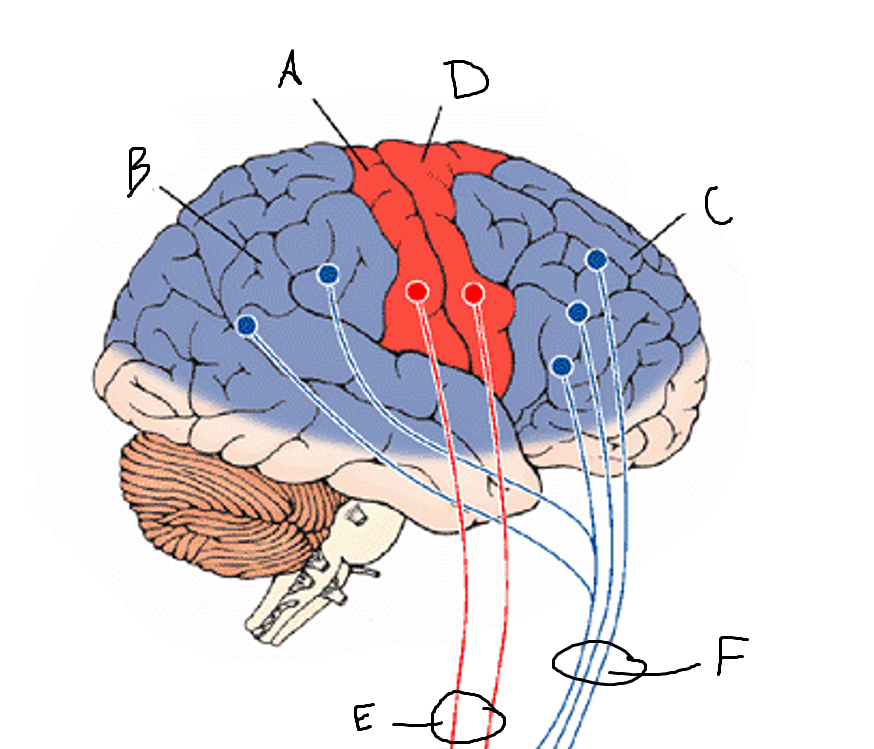

basal ganglia

A

somatosensory cortex

B

parietal association cortex

C

frontal and prefrontal cortices

D

primary motor cortex

E (where are the projections?)

putamen

F (where are the projections?)

caudate